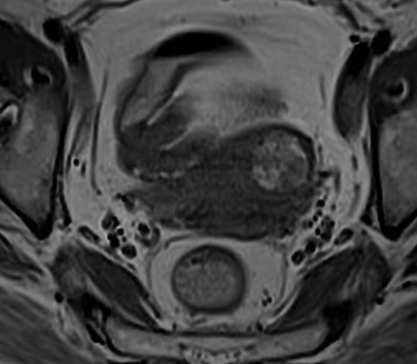

- Myomes avec composantes graisseuses

IRM